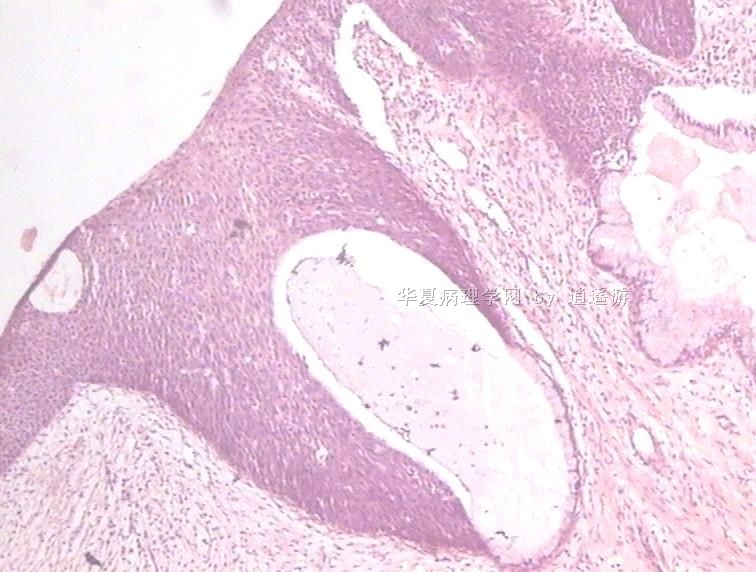

姓    名: ××× 性别:  女 年龄:  40

标本名称:  宫颈leep环切术切除组织

简要病史:  宫颈Ⅲ度糜烂

图1、2,10×,图3-6,4×,图7、8,40×

设备不够好,图像较模糊。

CIN3级累腺。

多看看是否有浸润,以及切缘。

CIN3级累腺,切缘是否干净?

CIN3级累腺

未见到浸润,但边缘看起来未切净。

同意.

很典型的.